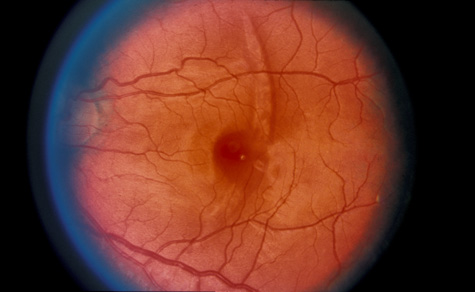

COMMOTIO RETINAE

Commotio retinae (Latin, meaning retinal contusion) is a contrecoup injury. It can occur peripherally (Fig. 8) or centrally, in which case it is called Berlin's edema (Fig. 9). Immediately and for several hours after the trauma, the retina appears normal, although the patient may complain of decreased vision. Thereafter, the outer layers of affected retina become opaque. On fluorescein angiography, the opaque retina blocks background choroidal fluorescence, and in most cases there is no leakage into or under the retina (Fig. 10). For years, clinicians had difficulty explaining this blockage, because leakage is expected in conditions with edema. It was then shown in experimental animals and in human autopsy eyes that Berlin's edema is not true edema. The retinal opaqueness is the result of intracellular edema and fragmentation of the photoreceptor outer segments and intracellular edema of the underlying pigment epithelium. There is little or no intercellular fluid.66–69

Fig. 8. Peripheral commotio retinae. The retinal blood vessels are clearly seen because the retinal whitening is in the outer retinal layers.

Fig. 9. Commotio retinae in the macula (Berlin's edema). The visual acuity was 20/25 at the time of the photograph and later improved to 20/15.

Fig. 10. A: Commotio retinae in the macula. B: On the angiogram there is no leakage in the area of commotio retinae.

The visual acuity in commotio retinae varies from 20/20 to 20/400 and does not always correlate with the degree of retinal opacification. There is no known treatment. The prognosis is usually excellent except in cases with associated subfoveolar choroidal rupture and in cases with choroidal rupture with subfoveolar hemorrhage. Poor visual recovery can also be expected in cases with severe retinal pigment epithelial damage. Serous retinal detachment (Fig. 11) signals this condition, which can be confirmed by leakage of fluorescein into the subretinal space.70